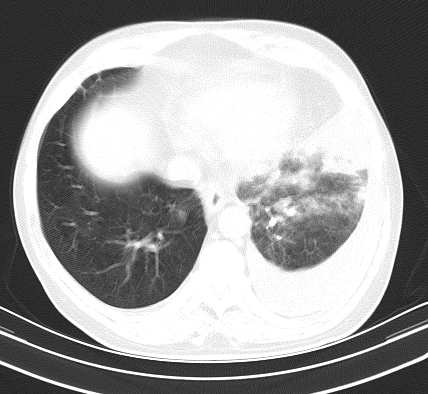

以下是引用老爱克斯新网客在2008-7-31 6:30:00的发言:[br]左肺上叶大片状病灶,左肺上叶支气管狭窄呈鼠尾状,左肺门增大,纵隔内见肿大淋巴结,左侧胸腔积液,余肺清晰。左肺中心型肺癌淋巴结转移,

以下是引用zjb在2008-7-31 6:32:00的发言:[br]左侧中心性肺癌 阻塞性肺炎 肺不张 胸腔积液 建议气管镜

以下是引用zjzjr在2008-7-31 8:45:00的发言:[br]考虑左侧中心性肺癌伴阻塞性肺炎,左肺上叶肺不张,纵隔淋巴结转移;左侧胸腔积液。建议行纤支镜检查。

以下是引用sdzyy在2008-7-31 8:47:00的发言:[br]病灶较治疗前有所进展,胸水增多, 左侧中心性肺癌 并 阻塞性肺炎 肺不张 胸腔积液 可能性大; 建议气管镜检查。 [br] [br]